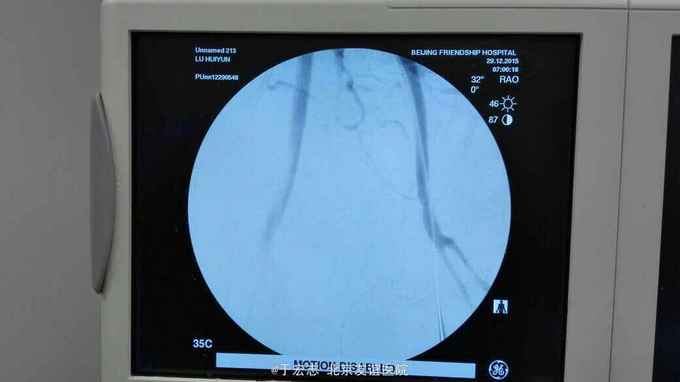

全腔内技术操作,用8F rotarex机械取栓导管操作,术前留置股静脉鞘,边操作边放静脉血,减少毒素吸收。静脉血经自体血回收处理。 操作完成后以血管缝合器缝合股动脉穿刺点,加压包扎。 患者转重症医学科途中出现心跳骤停,于手术室心外按压2小时复苏成功,转重症医学科血滤治疗。术后五小时生命体征均可维持,但家属还是放弃进一步治疗转运回当地治疗。

患者转运返家途中死亡。